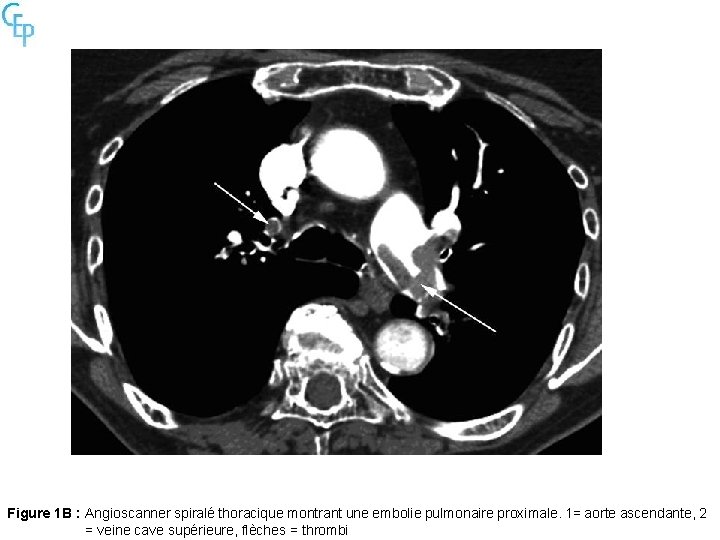

Figure 1 B : Angioscanner spiralé thoracique montrant une embolie pulmonaire proximale. 1= aorte ascendante, 2 = veine cave supérieure, flèches = thrombi